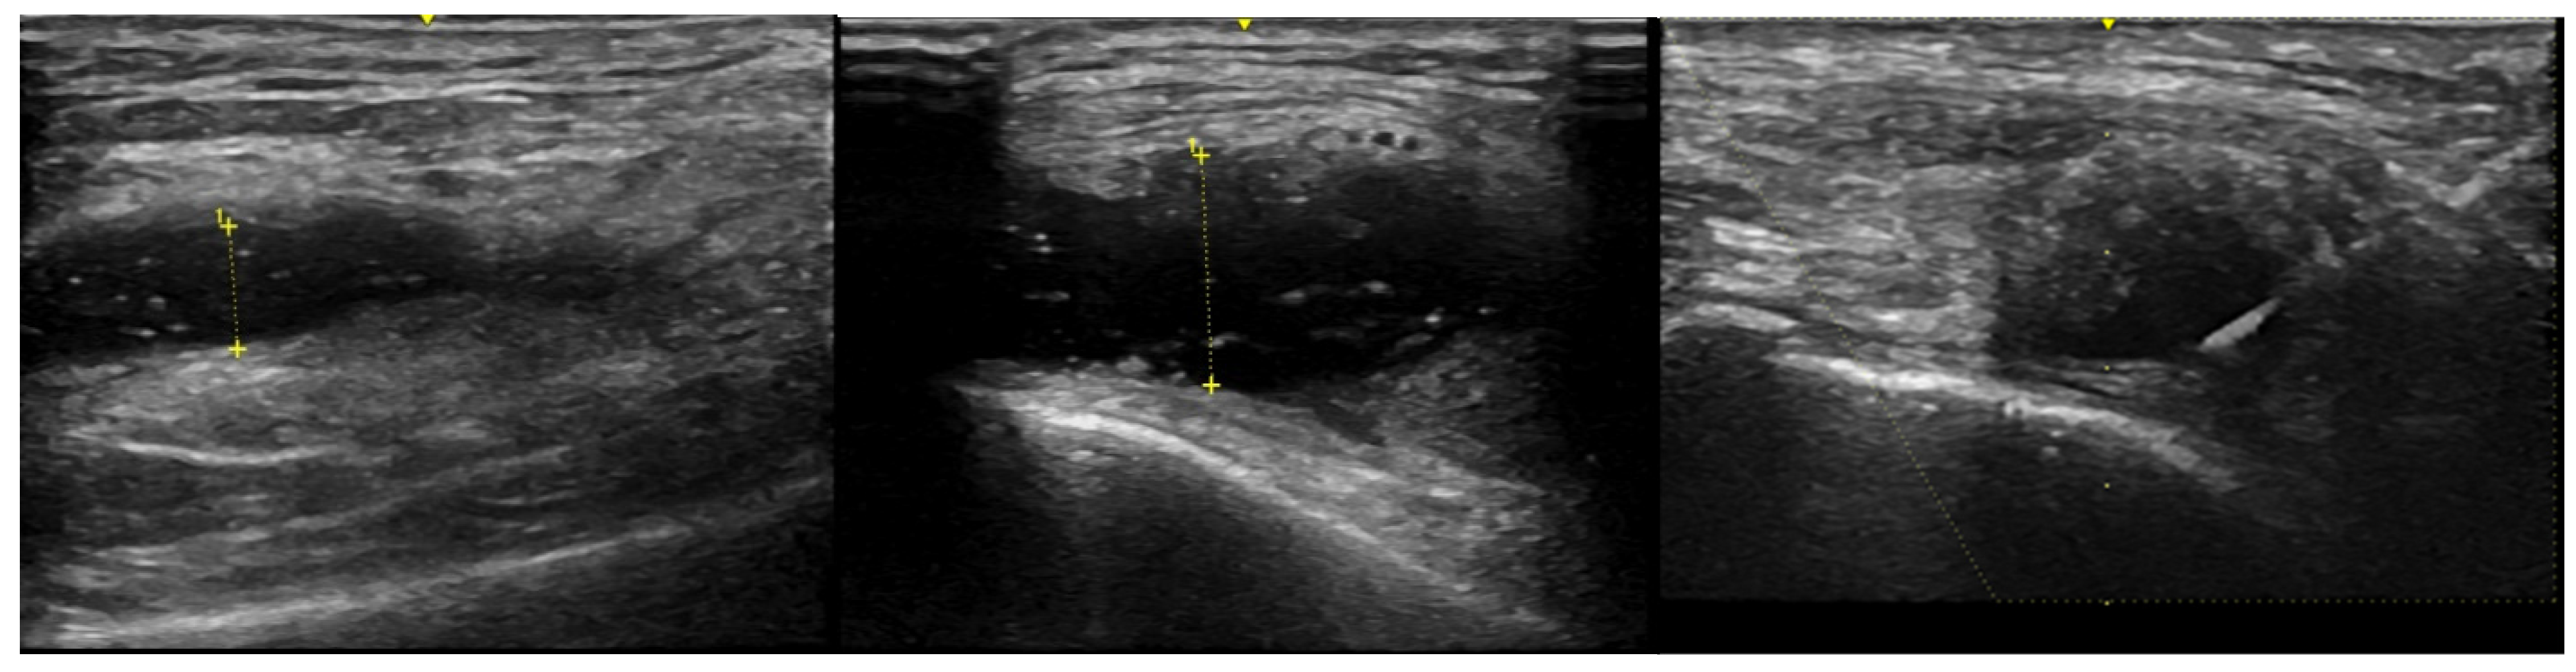

- Meehan, R.; Wilson, C.; Hoffman, E.; Altimier, L.; Kaessner, M.; Regan, E.A. Ultrasound measurement of knee synovial fluid during external pneumatic compression. J. Orthop. Res. 2019, 37, 601–608. [Google Scholar] [CrossRef] [PubMed]

- Block, J.; Berkoff, D.J.; Miller, L. Clinical utility of ultrasound guidance for intra-articular knee injections: A review. Clin. Interv. Aging 2012, 7, 89–95. [Google Scholar] [CrossRef]

- Bhavsar, T.B.; Sibbitt, W.L.; Band, P.A.; Cabacungan, R.J.; Moore, T.S.; Salayandia, L.C.; Fields, R.A.; Kettwich, S.K.; Roldan, L.P.; Emil, N.S.; et al. Improvement in diagnostic and therapeutic arthrocentesis via constant compression. Clin. Rheumatol. 2017, 37, 2251–2259. [Google Scholar] [CrossRef]